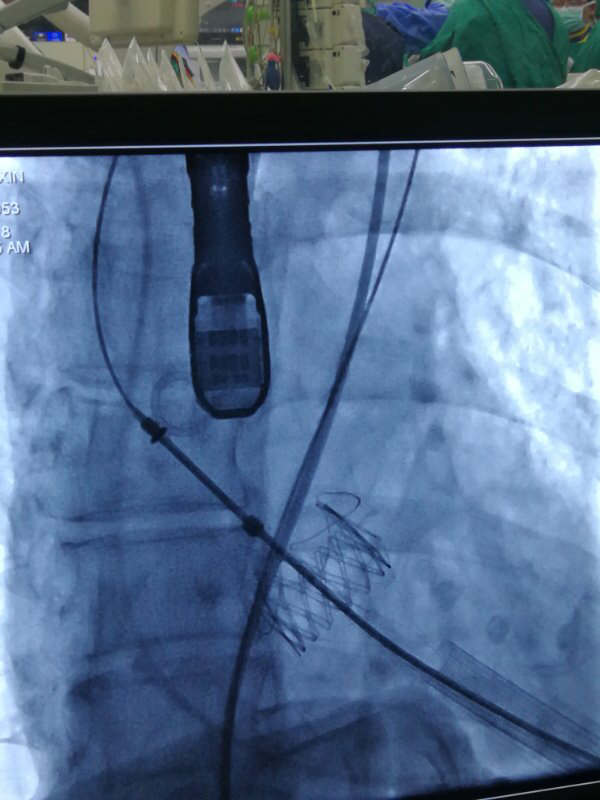

术中,在TAVI心脏手术团队的协作下,首先在患者心尖部位开一小孔,然后操控一根细长的输送鞘,将人工生物心脏瓣膜送入患者心腔。在造影屏幕监视下,新瓣膜被准确定位和放置于病变主动脉瓣位置。原来的心脏泵血“阀门”因关不紧“漏水”,新瓣膜“安装”完毕后,就像一扇运行良好的新“阀门”,一张一合地开始工作了。

图片说明:造影评估主动脉根部结构。

图片说明:人工瓣膜释放。

图片说明:人工瓣膜释放完成。